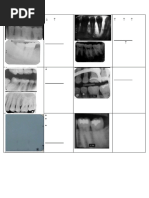

1.Blurred image ❑ The cause of the error

movement of the patient, film or machine

2.RO artifact ❑ The cause of the error

metallic objects

3. Phalangioma ❑ The cause of the error

Patient finger is placed in front of the film

B. Film placement errors

1. Double ❑ The cause of the error

image Film exposed twice

2. Incorrect film ❑ The cause of the error

placement Incorrect film placement (& mention the wrong position)

3. Back side ❑ The cause of the error

film projection Film is projected with its back side

(Herring bone ❑ How to correct or overcome

defect) Proper film placement

4. Printed dot ❑ The cause of the error

artifact Printed dot placed apically

5. Crowns cut ❑ The cause of the error

off Less than (2-4)mm was left from occlusal or incisal edge

6. Apices cut off ❑ The cause of the error

More than (2-4)mm was left from occlusal or incisal edge

7. Dropped film ❑ The cause of the error

corner Film edge is not parallel to incisal or occlusal plane

8. Distortion ❑ The cause of the error

Over bending of the film due to over pressure by the pt’s finger while holding the

film

11. Area of ❑ The cause of the error

interest not area of interest is not centralized in the film

shown ❑ How to correct or overcome Canine not shown

1. Cone cut ❑ The cause of the error

Improper point of entry [ ROI ] not in the centre of the cone (improper coverage

of the film)

2. ❑ The cause of the error

Horizontal Incorrect horizontal angulation

3. ❑ The cause of the error

Elongation Low vertical elongation

4. ❑ The cause of the error

Shortening Steep vertical angulation